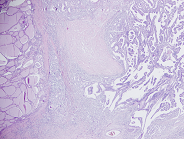

Olgu: 31 yaşında kadın hasta, postpartum 10. ayda dahiliye bölümüne adet görememe şikayetiyle başvurmuş. Tirotoksikoz saptanarak kliniğimize yönlendirilmiş. Özgeçmişinde özellik yok. Soygeçmişinde kız kardeşinde Graves hastalığı mevcut. FM›de TA 120/80mm/Hg, nabız 83 atım/dk. Laboratuvar değerleri TSH:<0,008mU/L(0,55-4,78), sT4:2,39ng/dl(0,89-1,76), sT3: 11,75ng/L(2,3-4,2), aTG: 2,7 IU/ml(<1,3), aTPO: 10235U/mL(<60), TSI: 6,34 IU/L(0,1-0,55), TSH reseptör antikoru:3,63IU/L(<1,5) idi. On gün sonra sağ tiroid loju üzerinde şiddetli ağrı şikayetiyle başvurdu. FM’de sağ tiroid loju hassastı. Tiroid ultrasonografisinde(US) sağ lob superior anteriorda 7x12x18mm ve sağ lob inferior anteriorda 5,5x10x15mm hipoekoik heterojen alan, sol lob superiorda 16x24x25mm kistik dejenerasyon alanları içeren izoekoik nodül, sol orta pol inferioru dolduran 22x38x44mm kistik dejenerasyon alanları içeren izoekoik nodül saptandı. TSH: <0,08mU/L, sT4:2,52ng/dl(0,89- 1,76), sT3: 15,5 ng/L(2,3-4,2), sedim: 46mm/saat (0-20), CRP: 8,4mg/L(0-5), WBC:13650(3,9-10,2x10⁹ idi. NSAII tedavisiyle ağrısı 1 hafta sonra geriledi. Sedim, CRP normale geldi. TSH:<0,008mU/L(0,55-4,78), sT4:3,05nd/dl(0,89-1,76), sT3: 18,93ng/L(2,3- 4,2) gelmesi üzerine metimazol tedavisi başlandı. TİİAB sitoloji sonucu sol orta ve inferioru dolduran nodül folliküler neoplazi şüphesi, hurtle hücreli tip ile uyumlu idi. Tiroid sintigrafisinde sol lobunda hipoaktif-kistik multinoduler, sol lobu hiperplazik tiroid bezi ile uyumlu bulgular mevcuttu. Bilateral total tiroidektomi operasyonu geçiren hastanın patolojisi Tiroid Papiller Karsinomu, infiltratif folliküler subtip, 0,4 cm çapında, sağ lob ile uyumlu geldi.